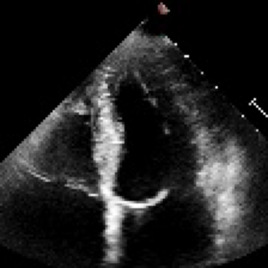

Accurate and consistent predictions of echocardiography parameters are important for cardiovascular diagnosis and treatment. In particular, segmentations of the left ventricle can be used to derive ventricular volume, ejection fraction (EF) and other relevant measurements. In this paper we propose a new automated method called EchoGraphs for predicting ejection fraction and segmenting the left ventricle by detecting anatomical keypoints. Models for direct coordinate regression based on Graph Convolutional Networks (GCNs) are used to detect the keypoints. GCNs can learn to represent the cardiac shape based on local appearance of each keypoint, as well as global spatial and temporal structures of all keypoints combined. We evaluate our EchoGraphs model on the EchoNet benchmark dataset. Compared to semantic segmentation, GCNs show accurate segmentation and improvements in robustness and inference runtime. EF is computed simultaneously to segmentations and our method also obtains state-of-the-art ejection fraction estimation. Source code is available online: https://github.com/guybenyosef/EchoGraphs.

翻译:对回声心电图参数的准确和一致预测对于心血管诊断和治疗十分重要,特别是左心室的分块可用于产生心血管体积、弹出分数(EF)和其他相关测量结果。在本文件中,我们提出一种新的自动化方法,称为EchoGraphs,用于预测弹出分数,并通过探测解剖关键点对左心室进行分解。根据图表变异网络(GCNs)进行直接协调回归模型用于检测关键点。GCNs可以学习根据每个关键点的局部外观以及所有关键点的全球空间和时间结构来代表心脏形状。我们在EchoNet基准数据集上对EchoGraphs模型进行了评估。与语系分化相比,GCNs显示了准确的分化和稳健度和推断运行时间的改进。EF是同时计算分解的,我们的方法也获得了最新化的弹射分数估计。源代码可在线查阅:https://github.com/guybenyos/Echophophs。